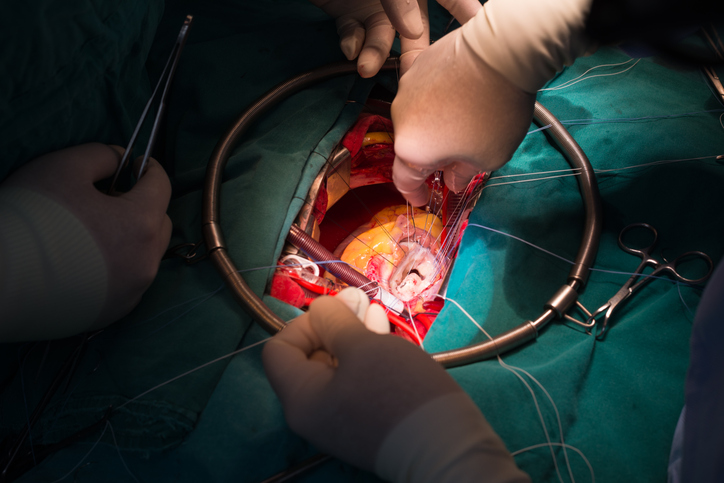

Elective mitral valve-in-valve procedures are tied to lower 3-year mortality, a large study finds.